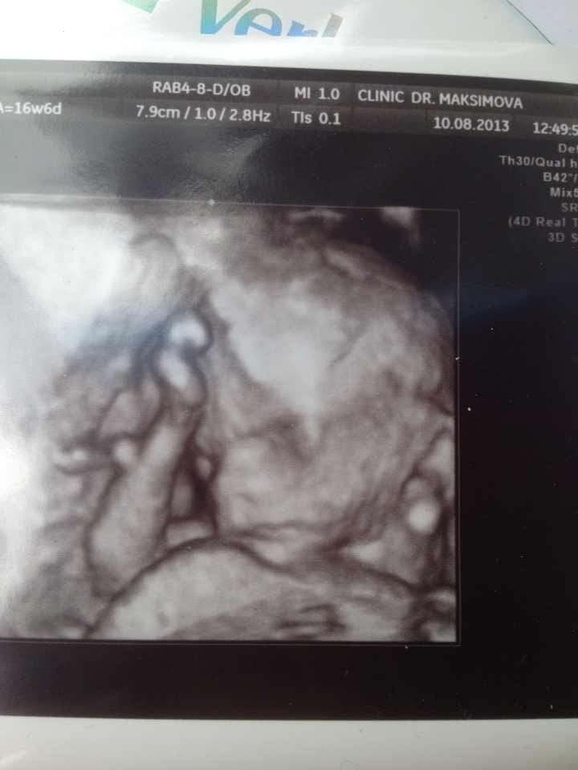

От счастья, были сегодня на узи. В последний момент возникла какая то паника)) а кто там?? А все ли в порядке??- ведь на учет я до сих пор не встала и никакие анализы не сдавала. И вот вернувшись с морей, побежала скорей смотреть крошку свою ненаглядную) поискала в интернете лучших узистов нашего города- выбирала по отзывам и чтоб не ждать долго записи. Максимова Ольга Геннадьевна принимает и в областной и в своем частном кабинете ( куда и попасть проще и аппарат там намного лучше) а цена такая же. Мы с мужем остались очень довольны- смотрела очень внимательно, учитывая что первый скрининг я не делала,включала сердцебиение,все показывала рассказывала.все у нас отлично)) все соответствует нормам и сроку.у нас 100% доченька!!! Доктор так и сказала- видите ничего не висит,вот две маленькие складочки-ДЕВОЧКА)) вот тут то слезки мои и побежали)))наша принцесса уже 16 см и 185 гр)) срок 16 нед и 2 дня. Дочурка уже похожа на папу очень- очень)!изображение отличное, видно все очень хорошо и все понятно где там что. С сынулькой я такого не видывала)) сделали фото 3 д и записали диск, тоже с фотками и видео.и теперь мои прыщики меня даже не печалят)) ведь там доченька)) все ей отдам и подарю, лишь бы здоровенькая была))в понедельник пойду в жк сдаваться.. Единственное что меня беспокоит помимо мелких прыщиков по всему лицу, так это головная боль- вот уже недели три как. Ни с того ни с сего появляется и уходит тоже так же, раз и перестала болеть..так ну и вес мой 54-55 ( обычный 50-52) все устраиваю себе разгрузочные дни))

И кисулюшка сладкая